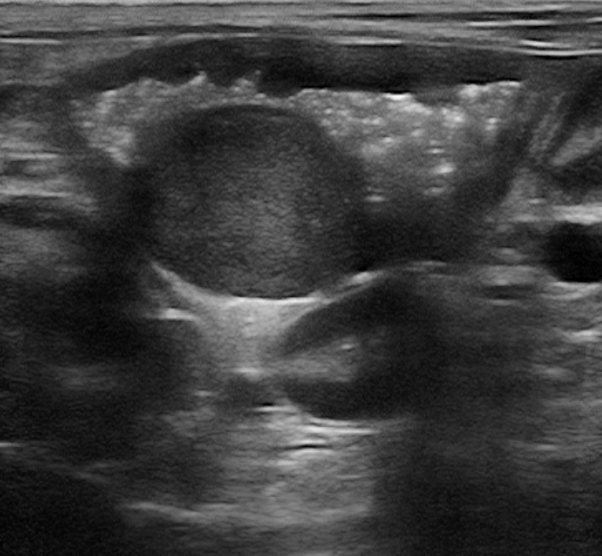

EVOLUÇÃO: INDICAÇÃO DE EXAME ULTRASSONOGRÁFICO

- Foi realizado exame ultrassonográfico abdominal que revelou presença de discreta quantidade de líquido livre em cavidade abdominal, linfonodos esplênico e mesentéricos acentuadamente aumentados e de ecotextura heterogênea. Visibilizou-se uma estrutura parenquimatosa aderida a um segmento de alça intestinal jejunal, homogênea, de formato ovalado, medindo 2,14cm x 1,44cm, vascularizada ao Doppler colorido e que invadia e obstruía parcialmente o lúmen intestinal, sugerindo processo neoplásico.

- Após uma semana foi realizado um novo exame ultrassonográfico para coleta de material citológico guiado pelo ultrassom. Neste novo exame a estrutura parenquimatosa havia aumentado de dimensões (2,96cm x 1,95cm), alguns segmentos de alças intestinais apresentaram plissamento e espessamento de parede. O fígado apresentou-se hipoecogênico e os linfonodos mesentéricos e esplênico permaneciam aumentados e heterogêneos.

Estrutura em alça 1º exame

Estrutura em alça 2º exame